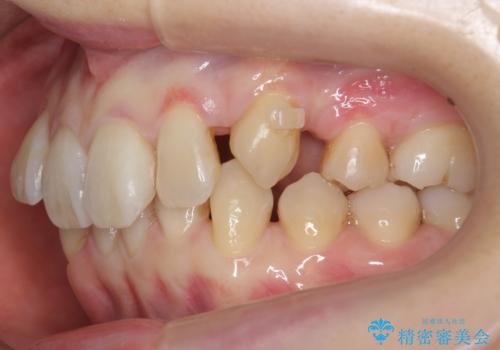

左上の犬歯が入りきらずねじれており、かみ合わせもずれていました。

左上の小臼歯を1本抜いて治療しています。

前歯は内側に傾いており(ラビッティング)、過蓋咬合(深いかみ合わせ)を呈していました。